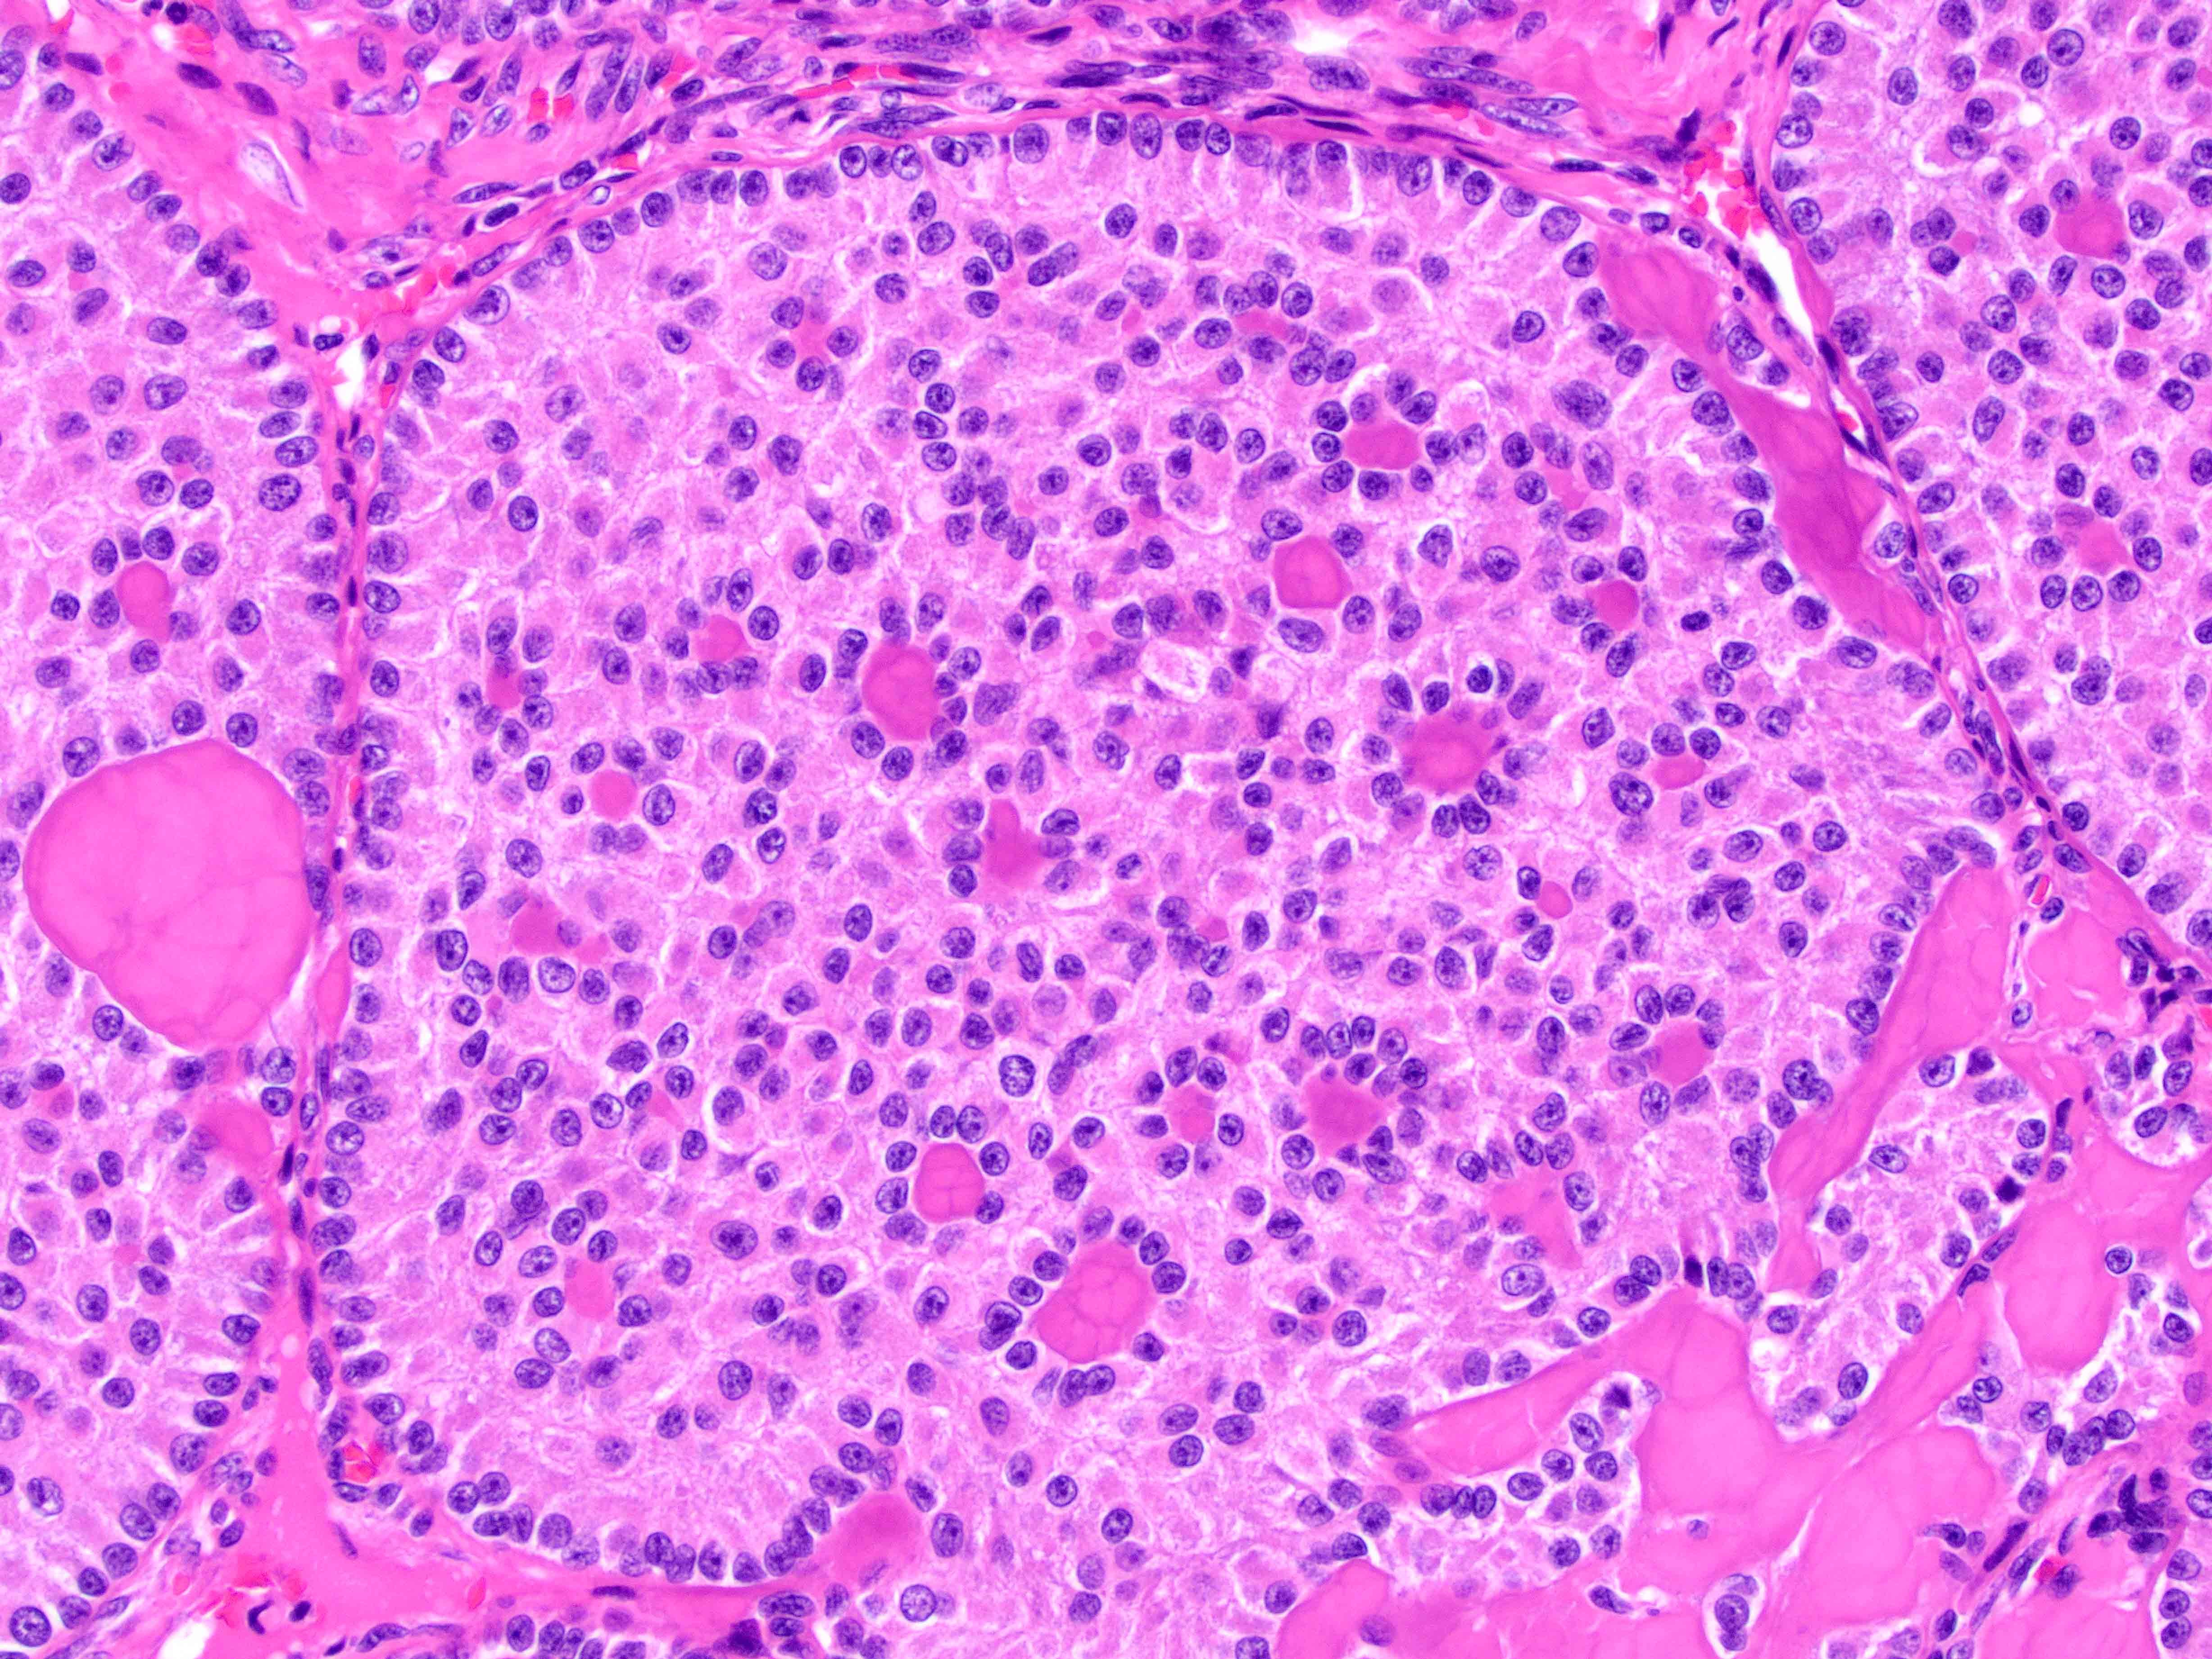

Case history:

This is a biopsy from the olfactory cleft (skull base) in a 71-year-old woman with...